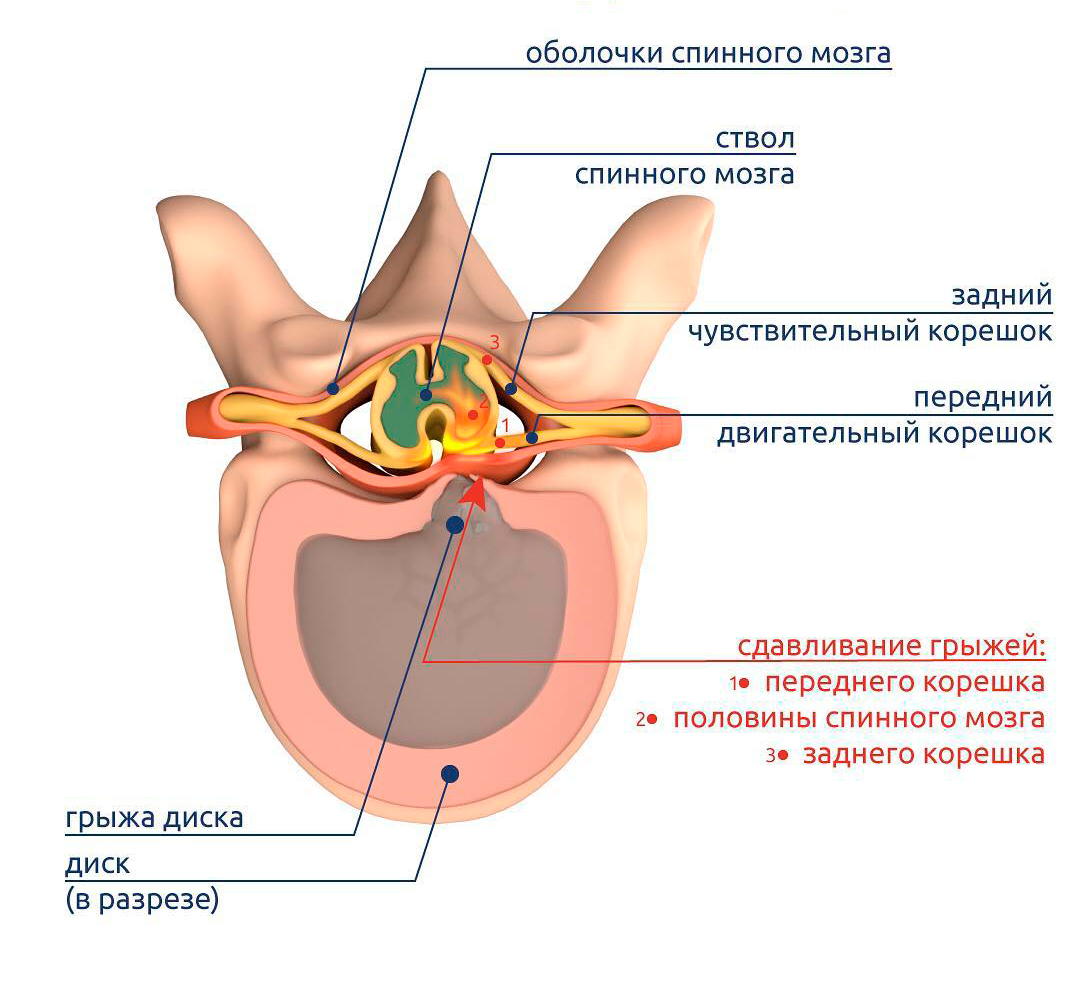

КТ-протрузии дисков: Визуализация и классификация